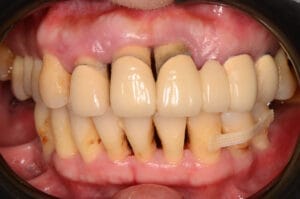

長期牙周病嚴重導致反覆的牙痛不適與進食困難,又恐懼牙科治療,尋求協助 牙周破壞嚴重,骨頭所剩不多,造